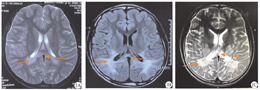

本例患儿入院当天体格检查:双侧瞳孔对光反射灵敏,颈强直呈阴性,双下肢肌张力稍增高,上肢可自行在床面移动,肌力查体不配合,腹壁反射引出,双膝反射正常;双侧克兰费尔特(Klinefelter)综合征及布鲁津斯基(Brudzinski)征呈阴性,双侧巴彬斯基(Babinski)征呈阳性;心、肺、腹部查体未见异常;不能自行行走、言语不清、可理解部分话语。辅助检查:血清促肾上腺皮质激素水平为389 pb/mL(正常参考值为<46 pb/mL),肾素水平为117.5 μIU/mL(正常参考值为2.8~39.9 μIU/mL),醛固酮水平为41.5 ng/dL(正常参考值为<23.6 ng/dL),均异常增高;8:00 am与16:00 pm皮质醇正常。头颅MRI显示,患儿双侧顶叶、颞叶脑白质区与侧脑室后角旁脑白质对称性异常信号影,累及双侧内囊后肢、双侧丘脑、胼胝体压部及大脑脚皮质脊髓束,见图1。

注:CCALD为儿童脑型X-连锁肾上腺脑白质营养不良

头颅MRI是CCALD患儿重要检测手段,发现CCALD病变时间远早于临床症状出现时间,典型表现为双侧顶叶、枕叶脑白质对称性病变,向前发展,可累及双侧内囊和颞叶后肢,向下发展,可累及脑干;若病变累及胼胝体压部,则双侧病变可合并,呈"蝴蝶样"。80% CCALD患儿头颅MRI提示初始病变位于顶叶、枕叶区深部脑室周围白质、胼胝体压部、皮质脊髓束、视觉和听觉通路[34,35,36],1%~2%起始于小脑白质甚至脑干[34,35];5%表现为双侧大脑不对称性受累,10%~15%为额叶受累。